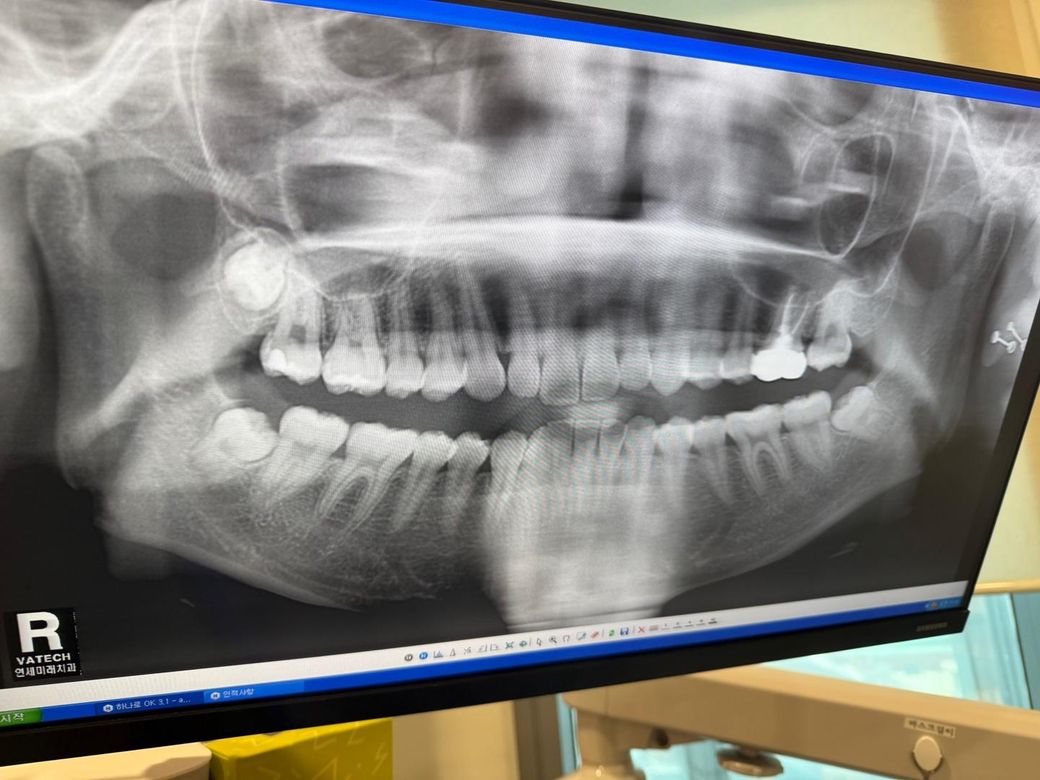

이 정도의 사랑니 대학 병원 가야 하나요..? (20대 여성)

오른쪽 위 상악 잇몸뼈에 걸쳐 있는데 너무 너무 무섭고 두려워요. 치과가 제일 싫은데..

정확한건 CT를 찍어봐야 알겟지만 신경과 겹쳐잇지만 않다면 발치 자체는 크게 어려울것같진 않습니다.

사진처럼 매복되어 있는 사랑인 발치를 할 필요가 없습니다. 사랑니는 잘못된 방향으로 맹출이 되거나 부분적으로 맹출되어 염증이나 불편감을 유발할 때 발치를 하면 됩니다. 너무 걱정하지 않으셔도 될 것으로 생각됩니다

우선 완전 매복되어 뼈 안에 있는 경우, 다른 치아에 미칠 영향이 적어보이는 경우에는 굳이 미리 뽑지는 않는데요. 일반치과에서 뽑으시려면 구강악안면외과 전문의 선생님께서 잘 뽑으시니 해당 전문의가 있는 치과로 내원하시면 되겠습니다.